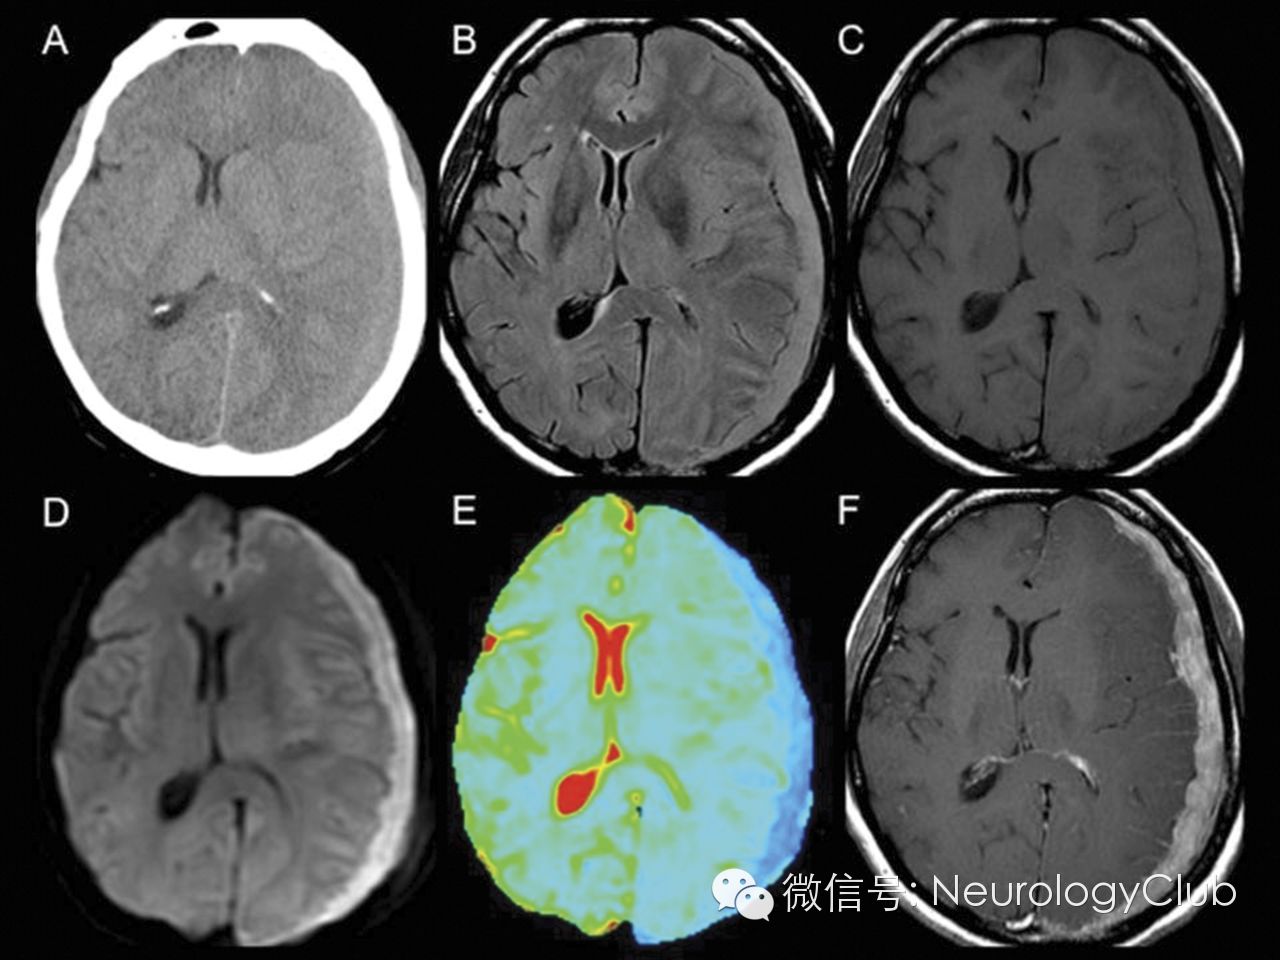

59岁女性,无外伤病史,表现为剧烈头痛及右侧肢体无力。

CT提示左半球等密度硬膜下积液,符合亚急性硬膜下血肿。患者行钻孔引流术时,神经外科医生发现硬膜下肉样组织,遂行活检。术后马上完善MRI检查,提示均匀细胞密集的硬膜下肿块。病理改变符合伯基特淋巴瘤(Burkitt lymphoma)。

图1:均匀的新月形病灶。CT等密度(A);FLAIR等信号(B);T1等信号(C);弥散受限(D:DWI;E:ADC);强化明显(F)